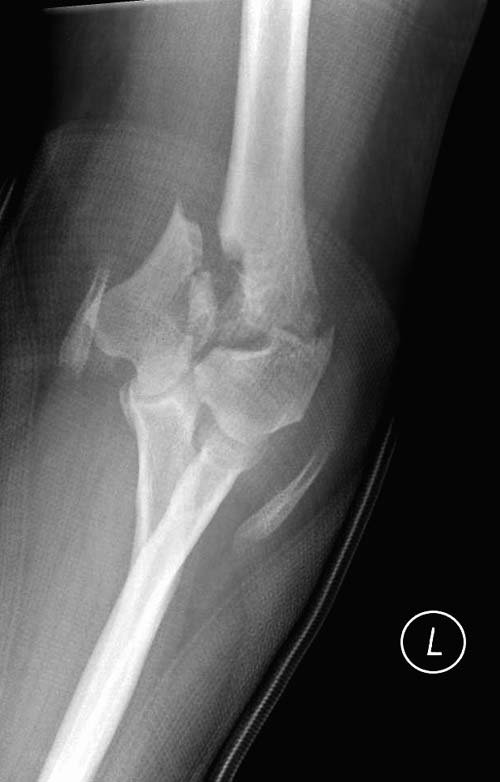

Здесь открытый перелом, временный наружный фиксатор и окончательная фиксация пластинами. Второй случай фиксация без остеотомии отростка пластинами Biomet-DePuy...